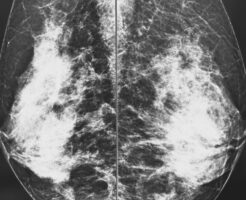

今日で、10月も終わり、今年も残すところ2か月となりました。 暑い日が長かったこともあり、夏の後、すぐ冬が来た感じに。。。 毎年、秋になると、乳がん検診を受けに行きます。 今日は、雨の中、運動もかねて、往復・・・